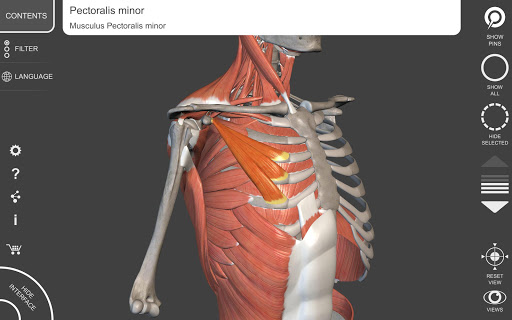

"Anatomy 3D Atlas" vous permet d'étudier l'anatomie humaine de manière simple et interactive.

Grâce à une interface simple et intuitive, il est possible d'observer chaque structure anatomique sous n'importe quel angle.

Les modèles anatomiques 3D sont particulièrement détaillés et avec des textures jusqu'à une résolution de 4k.

• Système musculo-squelettique

• Faites pivoter et zoomez chaque modèle dans l'espace 3D

• Option pour masquer ou isoler un ou plusieurs modèles sélectionnés

• Fonction de transparence

• En sélectionnant un modèle ou une épingle, le terme anatomique associé apparaît

• Description des muscles : origine, insertion, innervation et action